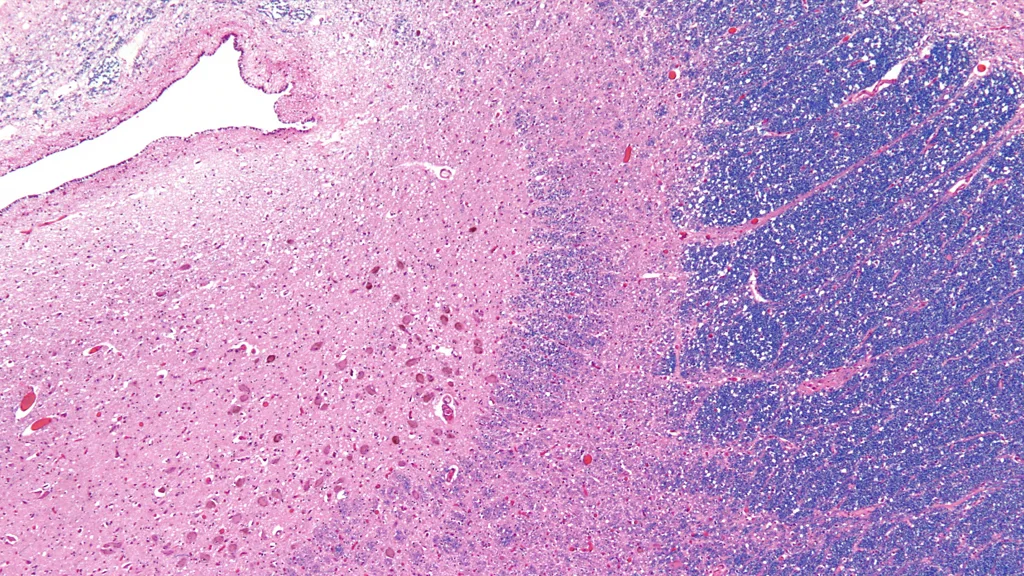

Përshkrimi është fjalë për fjalë: neuronët në locus coeruleus kanë ngjyrën e safirit për shkak të prodhimit të një neurotransmetuesi të veçantë të quajtur norepinefrinë. Kjo gjithashtu jep një tregues për funksionin e tij, pasi norepinefrina kontrollon gjendjen tonë të eksitimit fiziologjik dhe psikologjik.

Locus coeruleus ndodhet në trungun e trurit, pak mbi pjesën e pasme të qafës dhe përmban rreth 50,000 qeliza, një pjesë fare të vogël krahasuar me 86 miliardë neuronët që ka mesatarisht sistemi nervor qendror. Mjeku i Maria Antonetës, Félix Vicq d’Azyr, ishte i pari që e identifikoi në fund të shekullit të 18-të, por për një kohë të gjatë nuk tërhoqi shumë vëmendje.